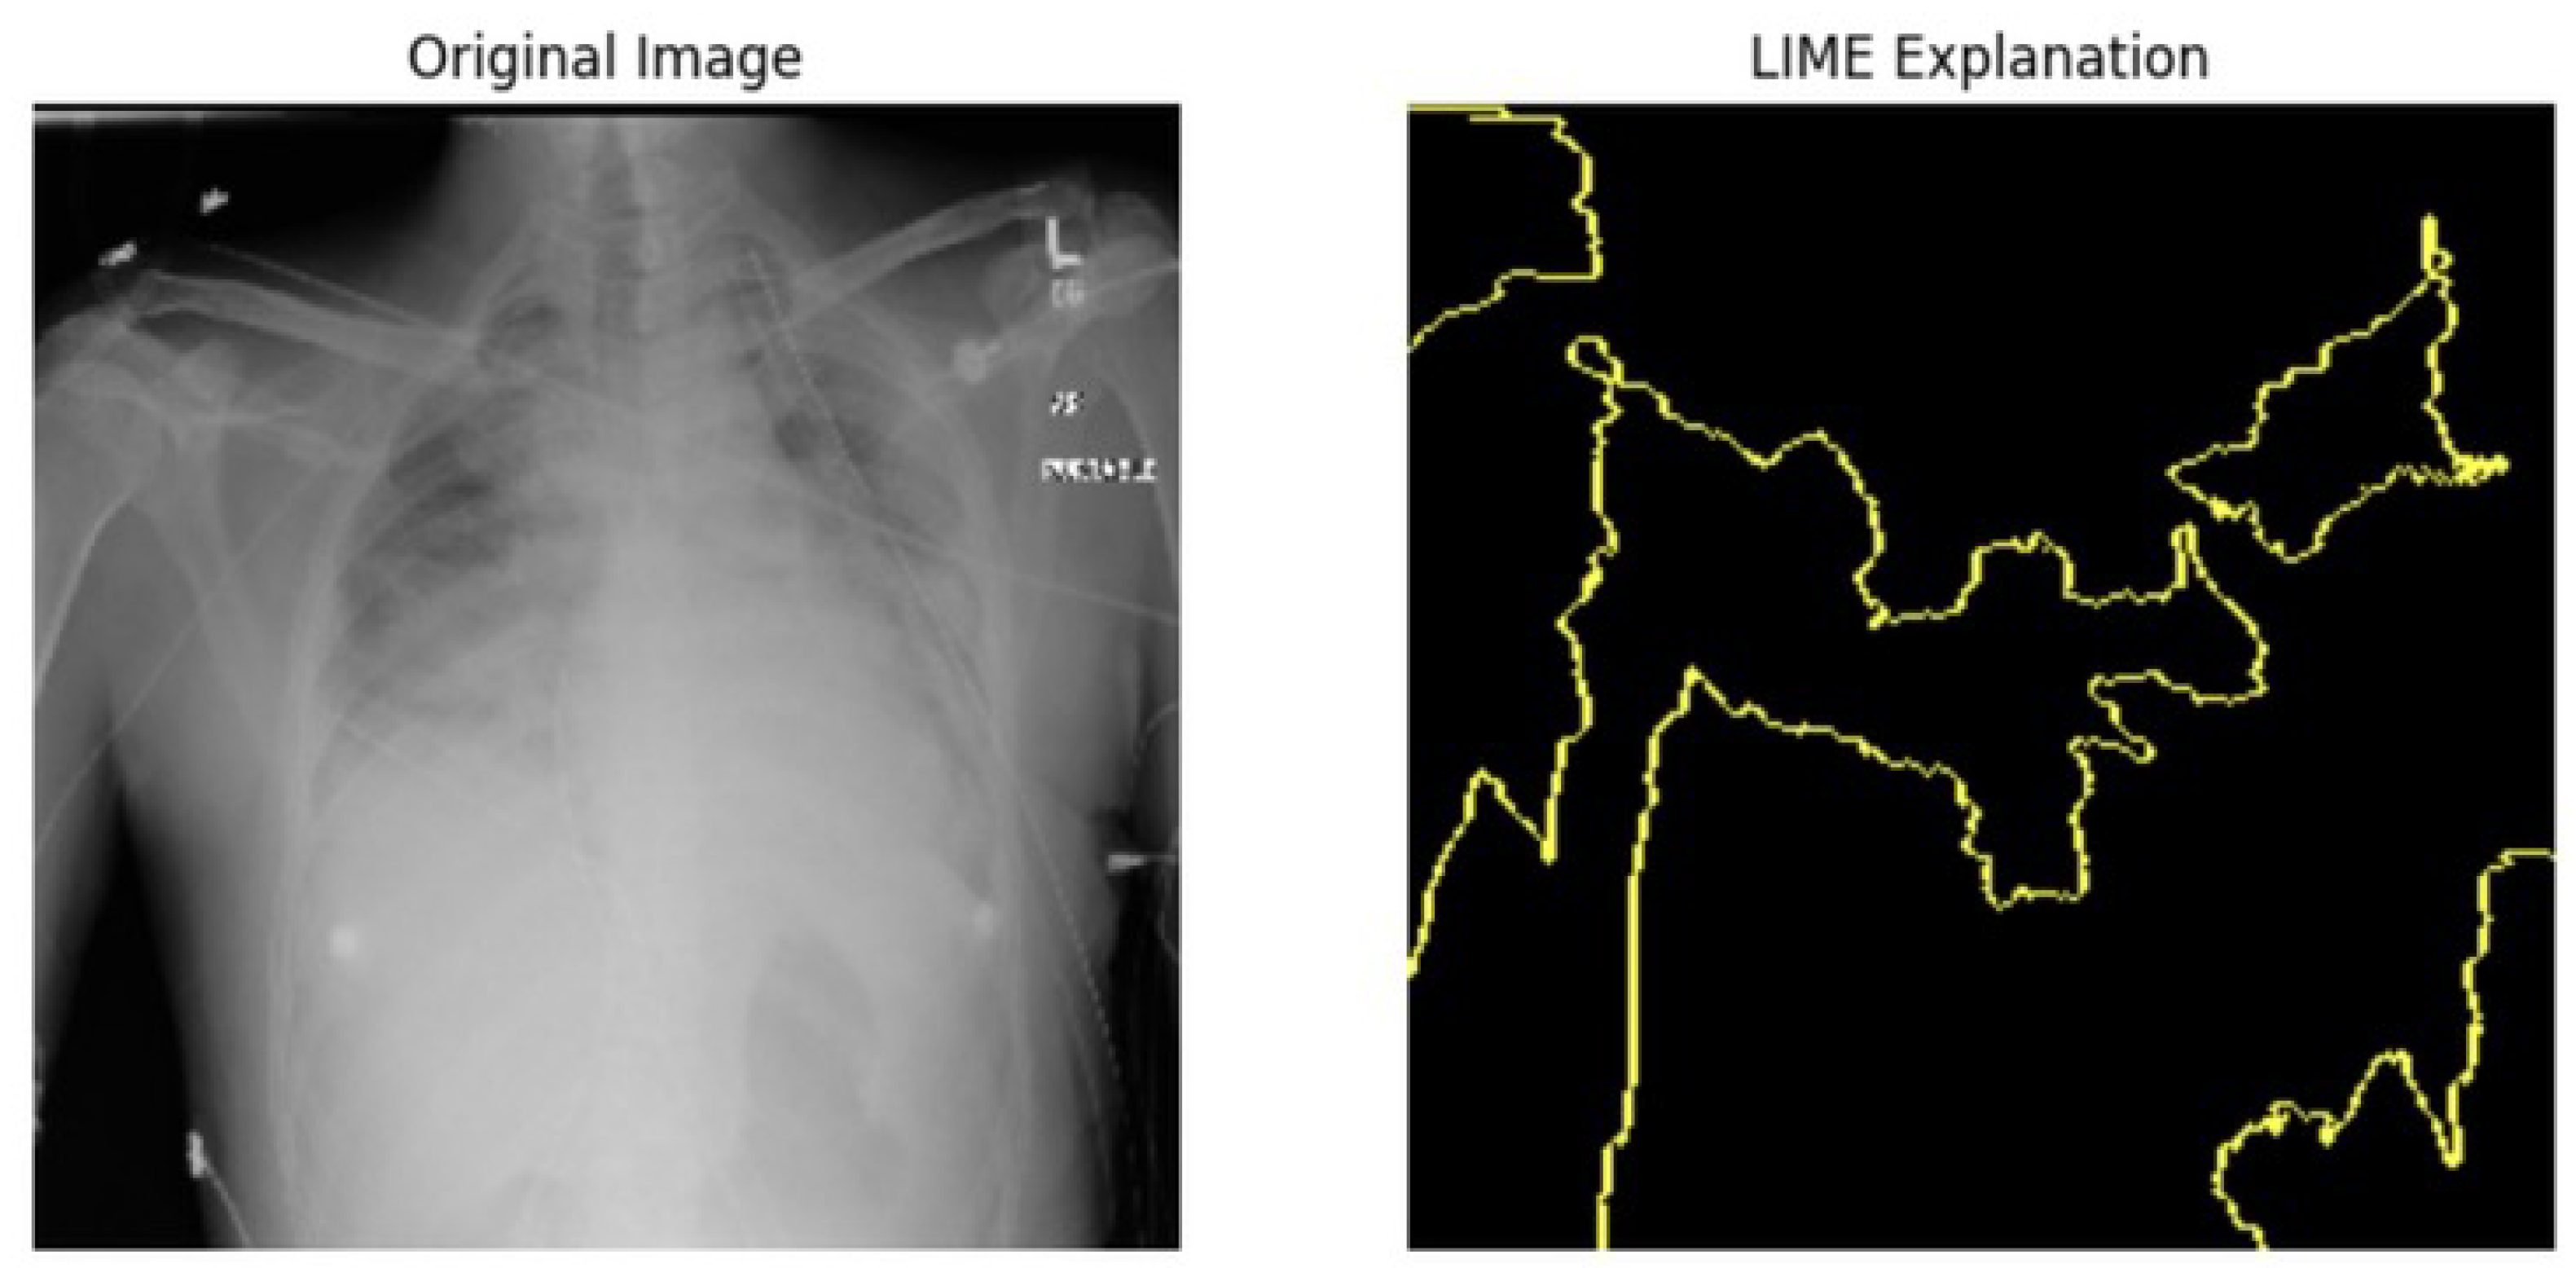

5.4.1. Local Interpretable Model-Agnostic Explanations for Clinical Validation

We applied scientific analysis on a random 7 sample, which was provided by the clinical specialist. The LIME Analysis for Image Data (a), (b), (c), (d), (e), and (f) is in Figure 22, Figure 23, Figure 24, Figure 25, Figure 26 and Figure 27. There are two parts of LIME analysis from the provided chest X-ray images to detect the disease area. Original Image and LIME explanation;

• Original Image: The patient’s thoracic cavity. It displays the typical anatomical structures of the chest, including the lungs, ribs, and heart.

• LIME Explanation: The result of applying LIME to the chest X-ray image. The yellow boundaries indicate the regions of the image that were most influential in the model’s decision-making process when determining whether the image indicated a particular condition. In this context, these regions are the parts of the X-ray that the AI model considered most important for making its diagnostic prediction.

The analysis very useful for clinicians to understand the model’s behavior and ensure that it aligns with medical expertise. The use of LIME helps in making the AI model’s interpretability decisions more transparent and interpretable. It allows medical professionals to verify whether the AI’s focus areas correspond to clinically significant regions. It also enhanced diagnostic capability of understanding which parts of the images in the AI model in refining the model further and ensures that it makes accurate and reliable predictions. This is particularly crucial in medical diagnostics where interpretability and accuracy are paramount.

Figure 23. LIME Analysis for Image Data (b) on original image to LIME explanation.